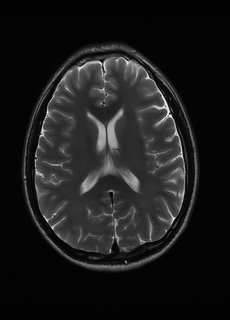

Sequence LR SISO MIMO MIMO tuned GT

λT1=6.63subscript𝜆subscript𝑇16.63\lambda_{T_{1}}=6.63 Refer to caption (a) 35.46/0.9431 Refer to caption (b) 40.82/0.9826 Refer to caption (c) 41.84/0.9857 Refer to caption (d) 42.12/0.9867 Refer to caption (e) PSNR/SSIM

λT2=2.11subscript𝜆subscript𝑇22.11\lambda_{T_{2}}=2.11 Refer to caption (f) 32.34/0.9254 Refer to caption (g) 36.19/0.9699 Refer to caption (h) 36.42/0.9711 Refer to caption (i) 36.78/0.9695 Refer to caption (j) PSNR/SSIM

λflair=8.00subscript𝜆𝑓𝑙𝑎𝑖𝑟8.00\lambda_{flair}=8.00 Refer to caption (k) 42.54/0.9489 Refer to caption (l) 45.24/0.9837 Refer to caption (m) 45.89/0.9868 Refer to caption (n) 46.35/0.9880 Refer to caption (o) PSNR/SSIM

Figure 4: Visual comparison of different recovery methods on real data